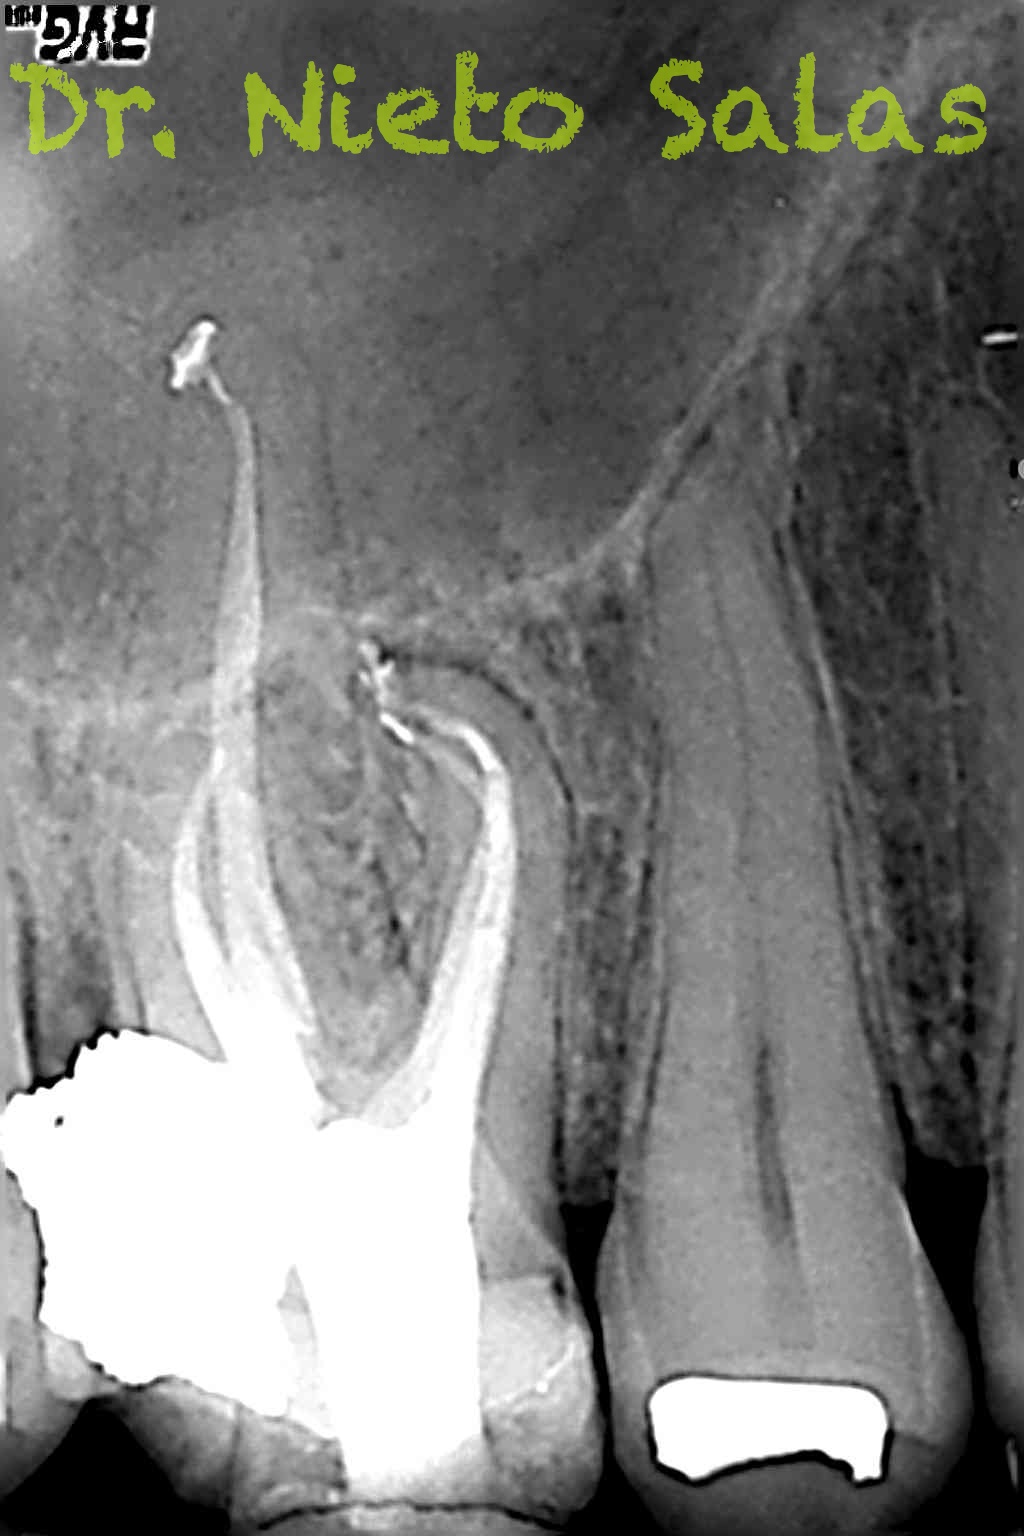

Os presento unos casos de varios molares superiores, con tres conductos mesiovestibulares con un foramen o con dos.

Una vez que tenemos medidas, obturamos los conductos:

No es habitual en nuestra práctica casos como estos, pero os pongo algunos más: